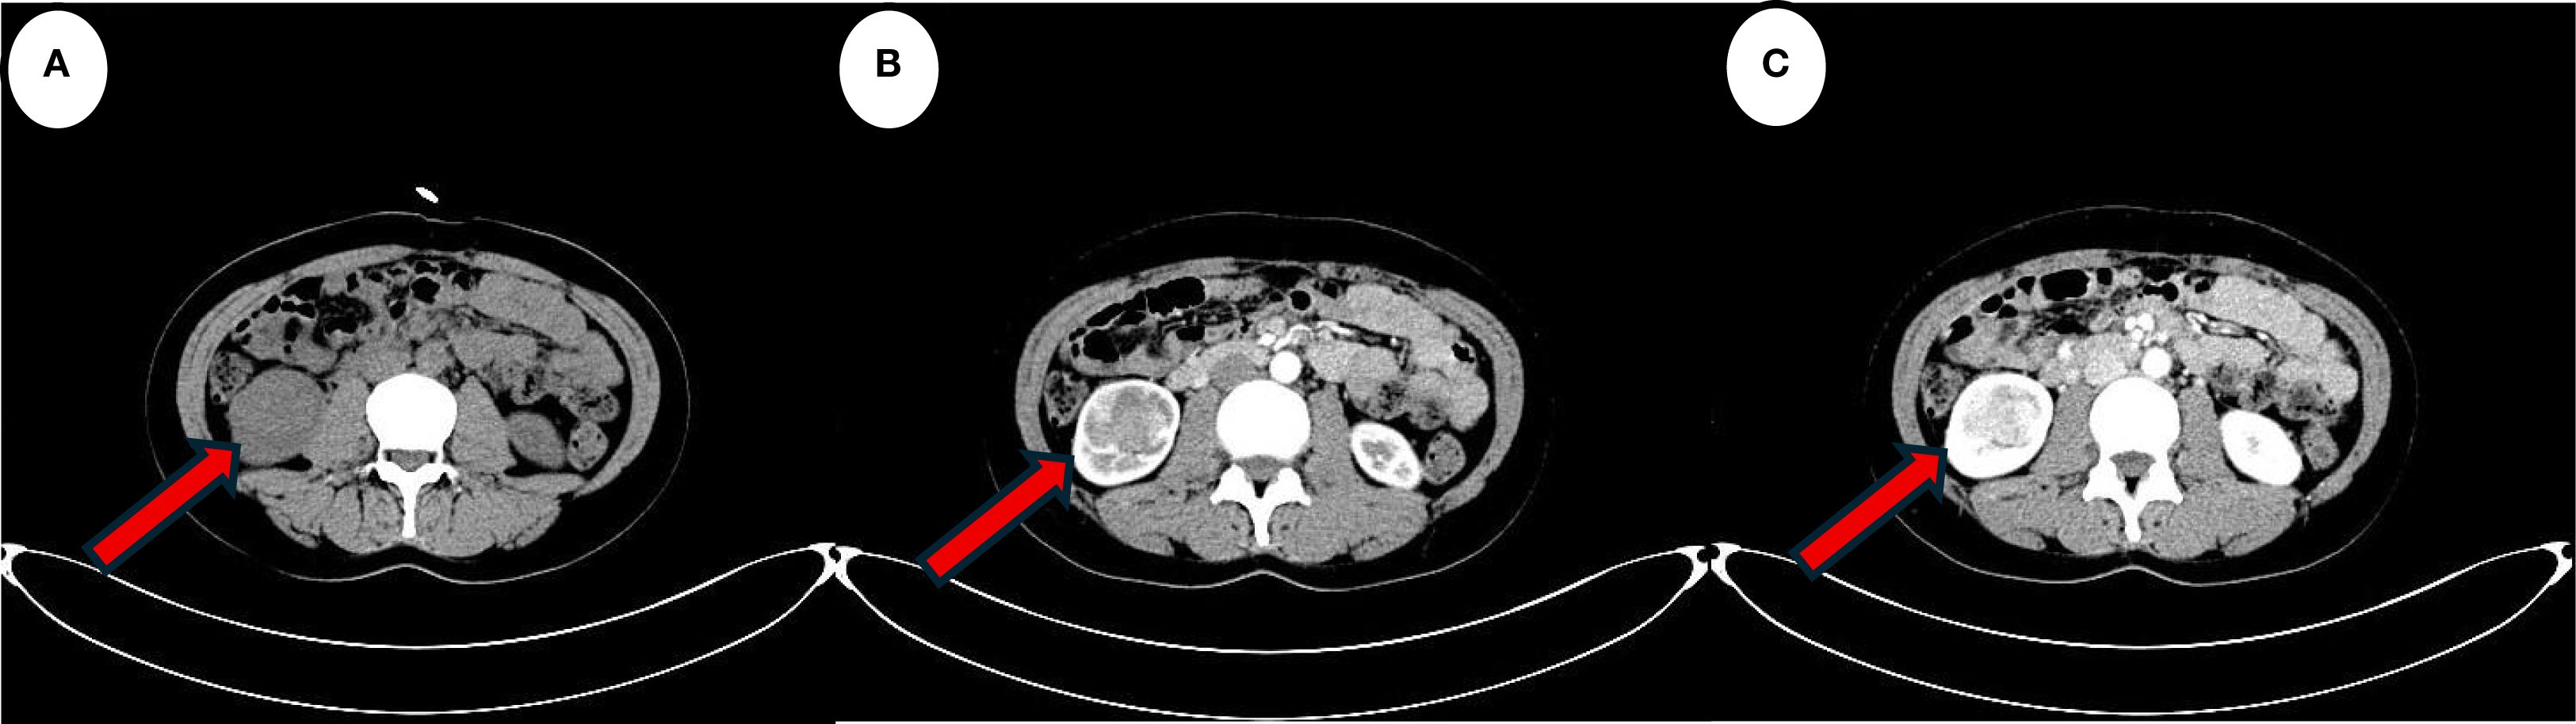

A 39-year-old female patient was admitted to the Department of Cardiovascular Medicine at the Affiliated Hospital of Zunyi Medical University due to inadequate blood pressure control. To exclude the possibility of secondary hypertension, she underwent bilateral adrenal computed tomography scanning and enhancement. The results indicated that the body of the left adrenal gland exhibited slight thickening, while the right adrenal gland did not demonstrate any abnormalities in size, morphology, or density (Figures 1A–C). No abnormal reinforcement was identified in the enhancement scans. The right renal mass with obvious inhomogeneous enhancement measured approximately 61×35 mm. The patient was admitted to the urology department for further evaluation and treatment. The patient’s blood pressure had previously been inadequately controlled during pregnancy 10 years ago. The possibility of hypertension in pregnancy had been considered in the external hospital. The patient’s blood pressure remained unstable after the end of the pregnancy. The patient has been regularly monitored and treated with oral antihypertensive medication to date. The patient had a medical history significant only for hypertension and one previous pregnancy. She denied any family history of genetic disorders. Both of her parents were healthy and had no history of hypertension. After admission to the urology department, her blood pressure ranged from 155–165/83–88 mmHg. Physical examination revealed no significant abnormalities, particularly with respect to the cardiovascular, renal, and neurological systems. Following a thorough preoperative evaluation that ruled out any surgical contraindications, the patient underwent laparoscopic partial right nephrectomy. Postoperative pathology (see Figures 2A–D) showed the presence of tumor in the right kidney and the tumor cells appeared in a circular polygon shape with HE staining, which was confirmed by immunohistochemical staining. The following markers were observed: CD34 (+), Vimentin (+), ERG (scattered +), SMA (partially +), GATA3 (partially +), CD10 (partially +), CD117 (scattered +), S-100 (scattered +), Syn (scattered +), Ki-67 (2%+). The following markers were found to be negative: CK, CK5/6, CK7, HMB45, CA9, Ksp-cadherin, Melan-A, p63, PAX-8, RCC, TFE3, CD56, CgA, CK18, CK8, NSE, Desmin. Subsequent to the surgical procedure, the patient’s blood pressure exhibited a gradual return to its norm. Following a comprehensive analysis of the patient’s clinical manifestations, imaging findings, and pathological results, a diagnosis of JGCT was rendered. It is noteworthy that the patient’s blood pressure has been effectively managed since the postoperative follow-up. During the 13-month outpatient follow-up, the patient reported well-controlled blood pressure and had discontinued oral antihypertensive medications. Repeated laboratory tests showed that renal function and serum potassium levels remained within normal limits. Follow-up abdominal CT and abdominal ultrasound examinations showed no evidence of tumor recurrence. In order to enhance the clarity of the case and the narrative flow, we have added a visual timeline of the patient’s course of illness (Figure 3).

Figure 1. The red arrow indicates the lesion. (A) Computed tomography scan suggests a localised hypodense occupancy of the right kidney. (B) A small amount of enhancement is seen in the cortical phase of the enhanced scan. (C) Enhancement is more obvious in the medullary phase. The features are consistent with the typical presentation of JGCT imaging.